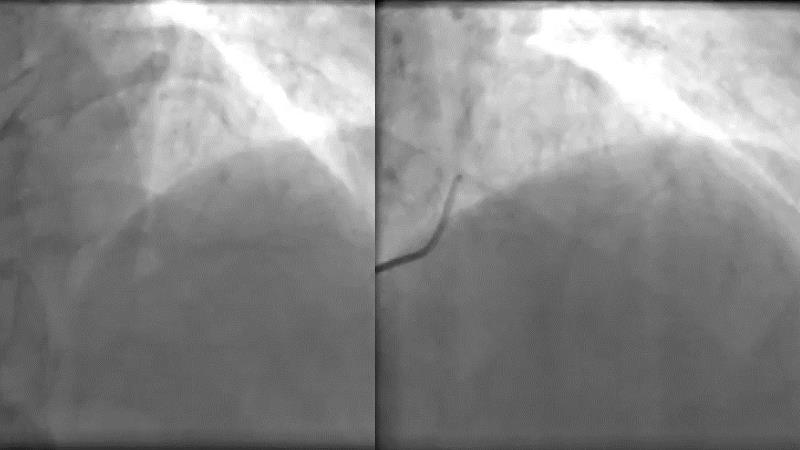

Complex coronary artery disease: can stents and DCB be complementary?

DES and DCB, can these two technologies be complementary for the treatment of the same patient? What are the advantages and how to proceed? You will know everything by watching this presentation based on concrete cases.